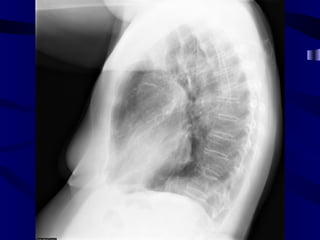

Indistinct Right Heart Border

Right Middle LobeAtelectasis